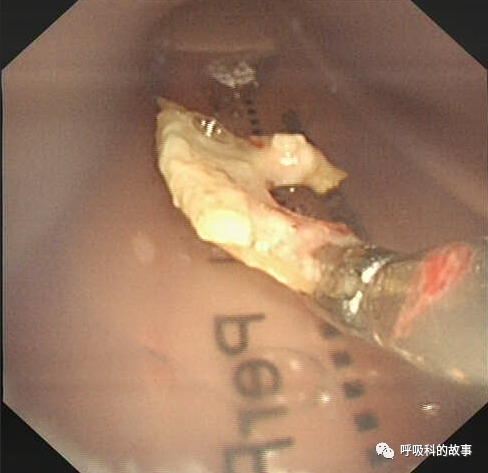

可是又經過了三週,黃女士症狀依舊沒有改善,這一次她終於聽話地住進了病房,我們給她做了氣管鏡檢查,結果發現右下葉支氣管開口有肉芽組織堵塞了管腔,將這些肉芽組織清理後,終於暴露出了一個骨性異物,最終我們將其鉗出。

對於慢性咳嗽不愈,CT顯示在同一部位反覆感染,氣管內有高密度影者,一定要警惕支氣管異物的可能,及時進行氣管鏡檢查。而患者也希望能充分配合醫生,才能及時解決病痛。